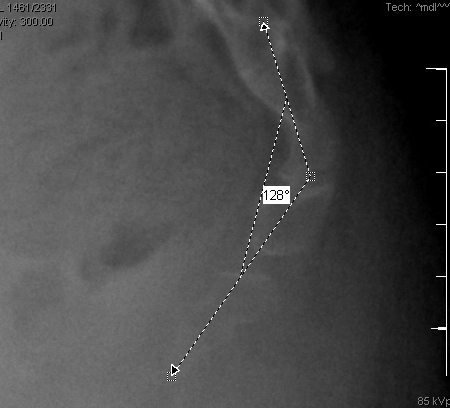

Radiografia sacrococcígea lateral dinâmica de um paciente com coccigodinia crônica idiopática, mostrando 30° de flexão anterior na posição sentada

Do acervo pessoal do Dr. R. Schrot